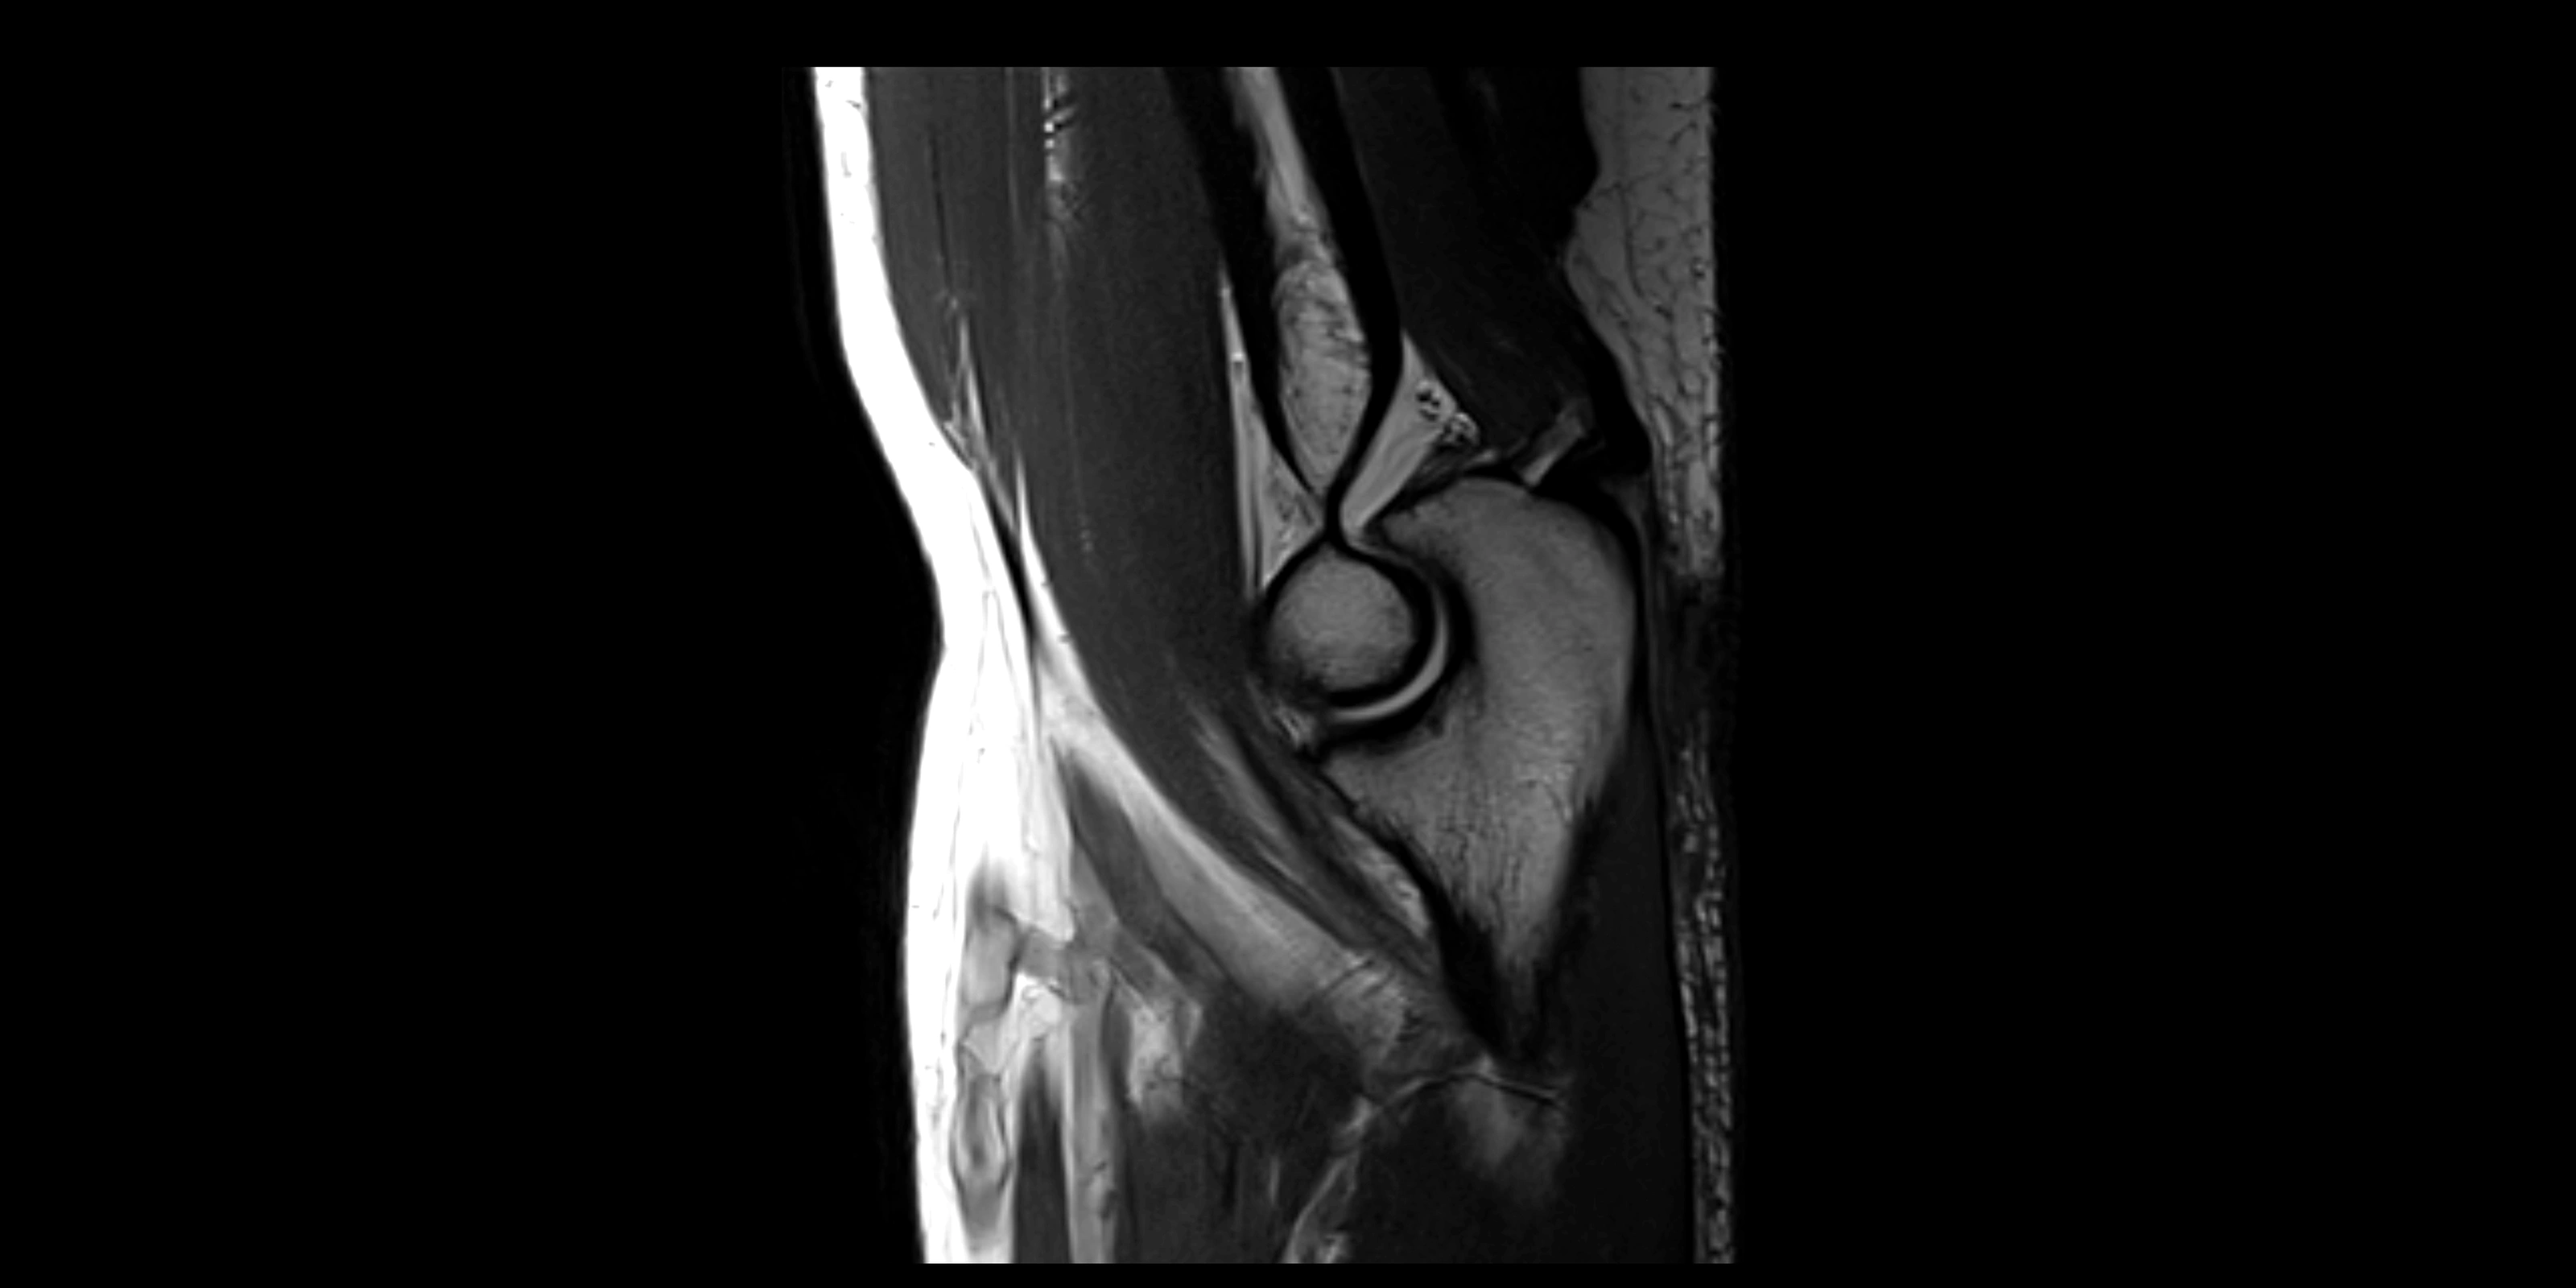

MRI Appearance

T1-weighted images:

• Ligament: low signal intensity (dark), appearing as a continuous band around the radial head.

• Adjacent fat and marrow: bright, creating contrast with the ligament.

• Thickening or disruption indicates injury or fibrosis.

• Joint capsule and synovium seen as thin low-signal lines contiguous with ligament margins.

T2-weighted images:

• Ligament: low signal (dark) with clear delineation from joint fluid.

• Fluid or edema: bright hyperintense, separating or surrounding the ligament in partial tears.

• Complete tear: discontinuity or non-visualization of ligament fibers, often with joint effusion.

STIR:

• Normal ligament: dark band encircling radial head.

• Pathology: bright hyperintense periligamentous signal suggesting edema, sprain, or partial tear.

Proton Density Fat-Saturated (PD FS):

• Normal: dark, well-defined band outlining the radial head.

• Partial tear: irregular or bright hyperintense signal within or adjacent to ligament fibers.

• Joint effusion and reactive synovitis appear bright and are well visualized.

MRI Arthrogram Appearance

• Contrast outlines the proximal radioulnar joint and radial head recess.

• Normal ligament appears as a dark ring surrounding the radial head, containing the injected contrast within the joint cavity.

• Partial tear: contrast extends along the ligament or beneath its fibers.

• Complete tear or subluxation: contrast extravasates around the radial head or ulna, indicating discontinuity.

• Detects capsular defects, instability, or synovial invagination with high sensitivity.